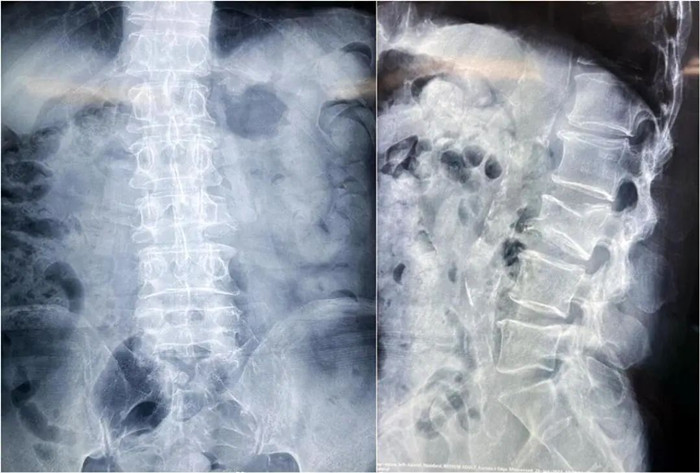

患者情況:腰椎L3壓縮性骨折

南京醫科大學第二附屬醫院骨科副主任醫師王伯堯帶領團隊成功完成經皮椎體球囊擴張成形術(PKP)。該患者為腰椎陳舊性壓縮性骨折,腰部疼痛難忍,活動受限,生活受到影響。王醫生借助普愛醫療大平板C臂機高清的圖像及靈活的擺位,快速定位椎弓根位置,確定進針點,使得手術得以更加高效和準確地完成。

患者術前影像